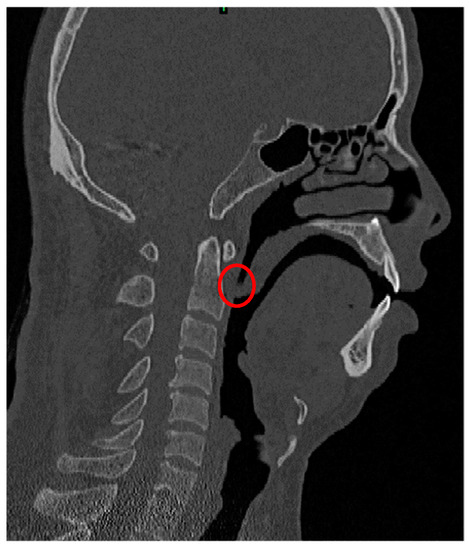

2.1. ETA Model with OSAHS